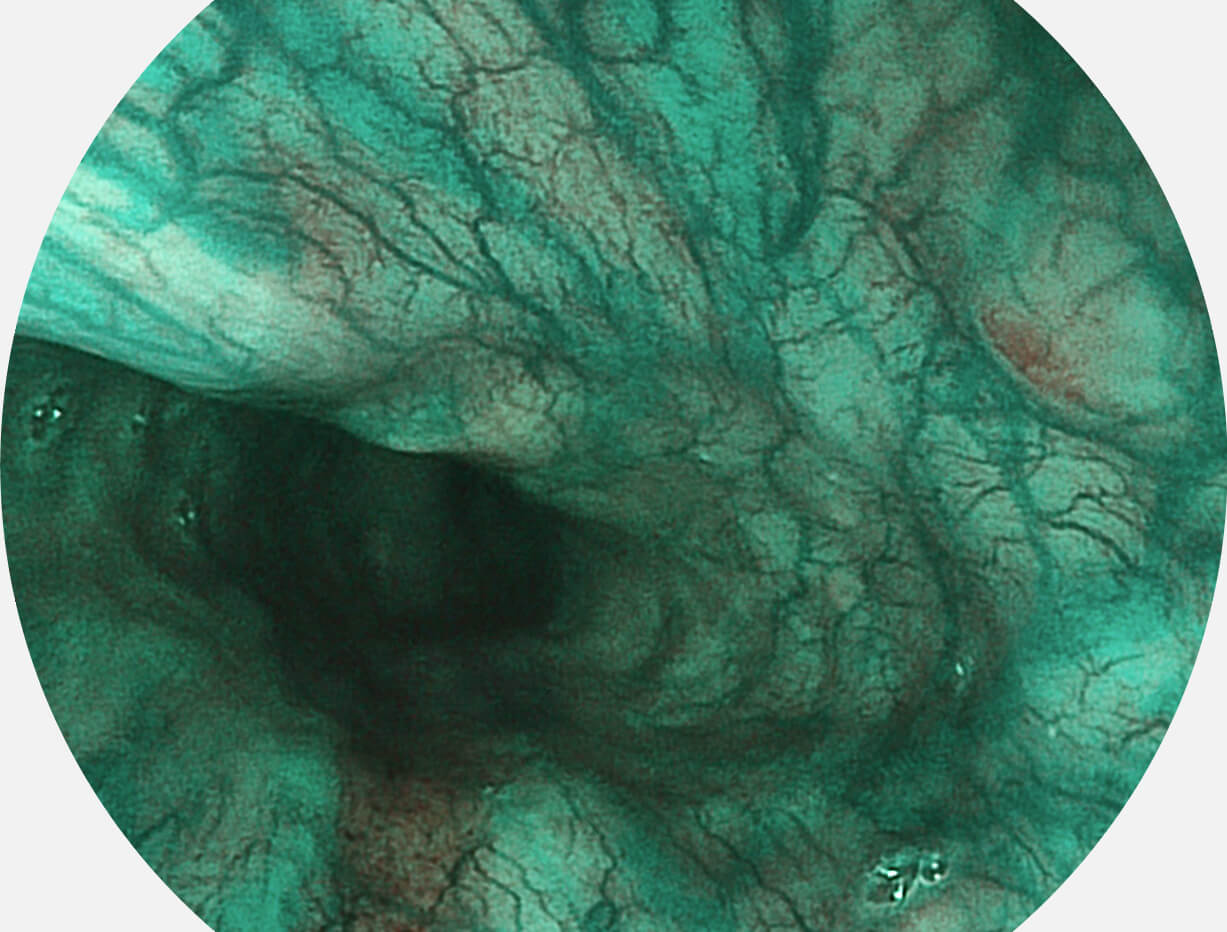

图像具有高亮度、高黏膜血管颜色对比度的特点,且不改变粘液、食物残渣、粪便的基本颜色,可在中远景下进行观察,助力消化道早期疾病的诊断。

SFI图像

采用光路合束技术,光谱自由度高,实现了更丰富的照明模式,染色模式SFI及VIST,从远景到近景,助力消化道早期疾病诊断。